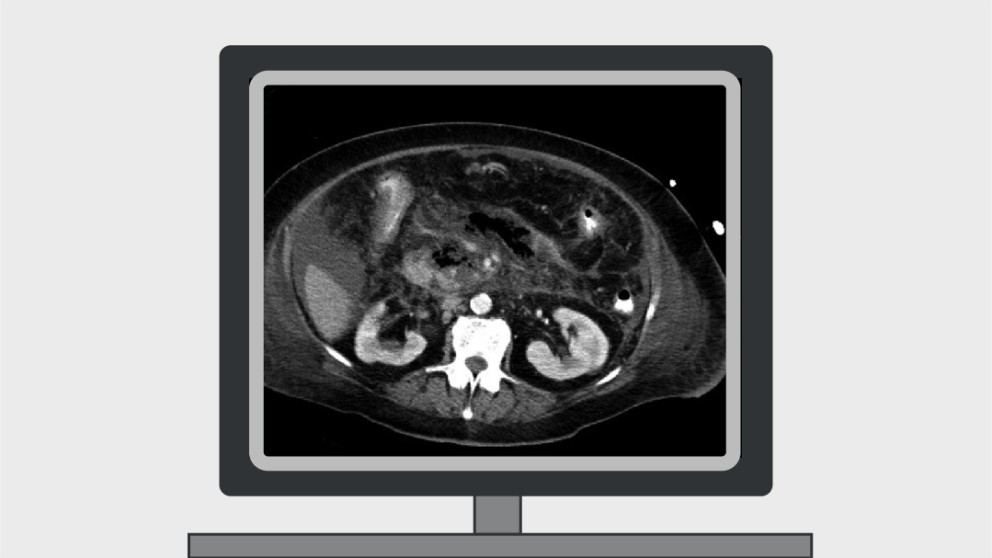

Chronic pancreatitis is a severe fibroinflammatory disorder of the pancreas that has a high associated morbidity and mortality. The number of hospitalizations for chronic pancreatitis has markedly increased and the global incidence of the disease continues to rise. Even though progress has been made in identifying common risk factors for chronic pancreatitis, the pathogenesis of the disease remains poorly understood.

This online course covers the definition of chronic pancreatitis, mortality, socioeconomic effect, aetiology and epidemiology, diagnosis and staging, management and the occurrence of bile duct obstruction and pseudocysts. Two clinical cases are also included, allowing application of knowledge in real-life scenarios.

Autoimmune pancreatitis (AIP) is a rare autoinflammatory condition of the pancreas that is steroid responsive. Correct diagnosis of patients who present with clinical features of AIP is key because AIP can mimic pancreatic cancer, a deadly disease, which is ten times more common.

All aspects of AIP—from its definition and epidemiology to its clinical presentation, subtypes, diagnosis, pathophysiology and treatment—are covered in this online course by Julia Mayerle and Georg Beyer.